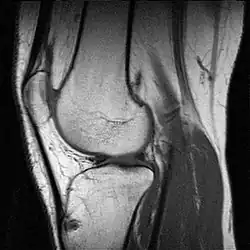

IRM d'un genou.

L'imagerie par résonance magnétique (IRM) permet d'observer tous les éléments de l'articulation. Elle est souvent réalisée en cas de rupture des ligaments